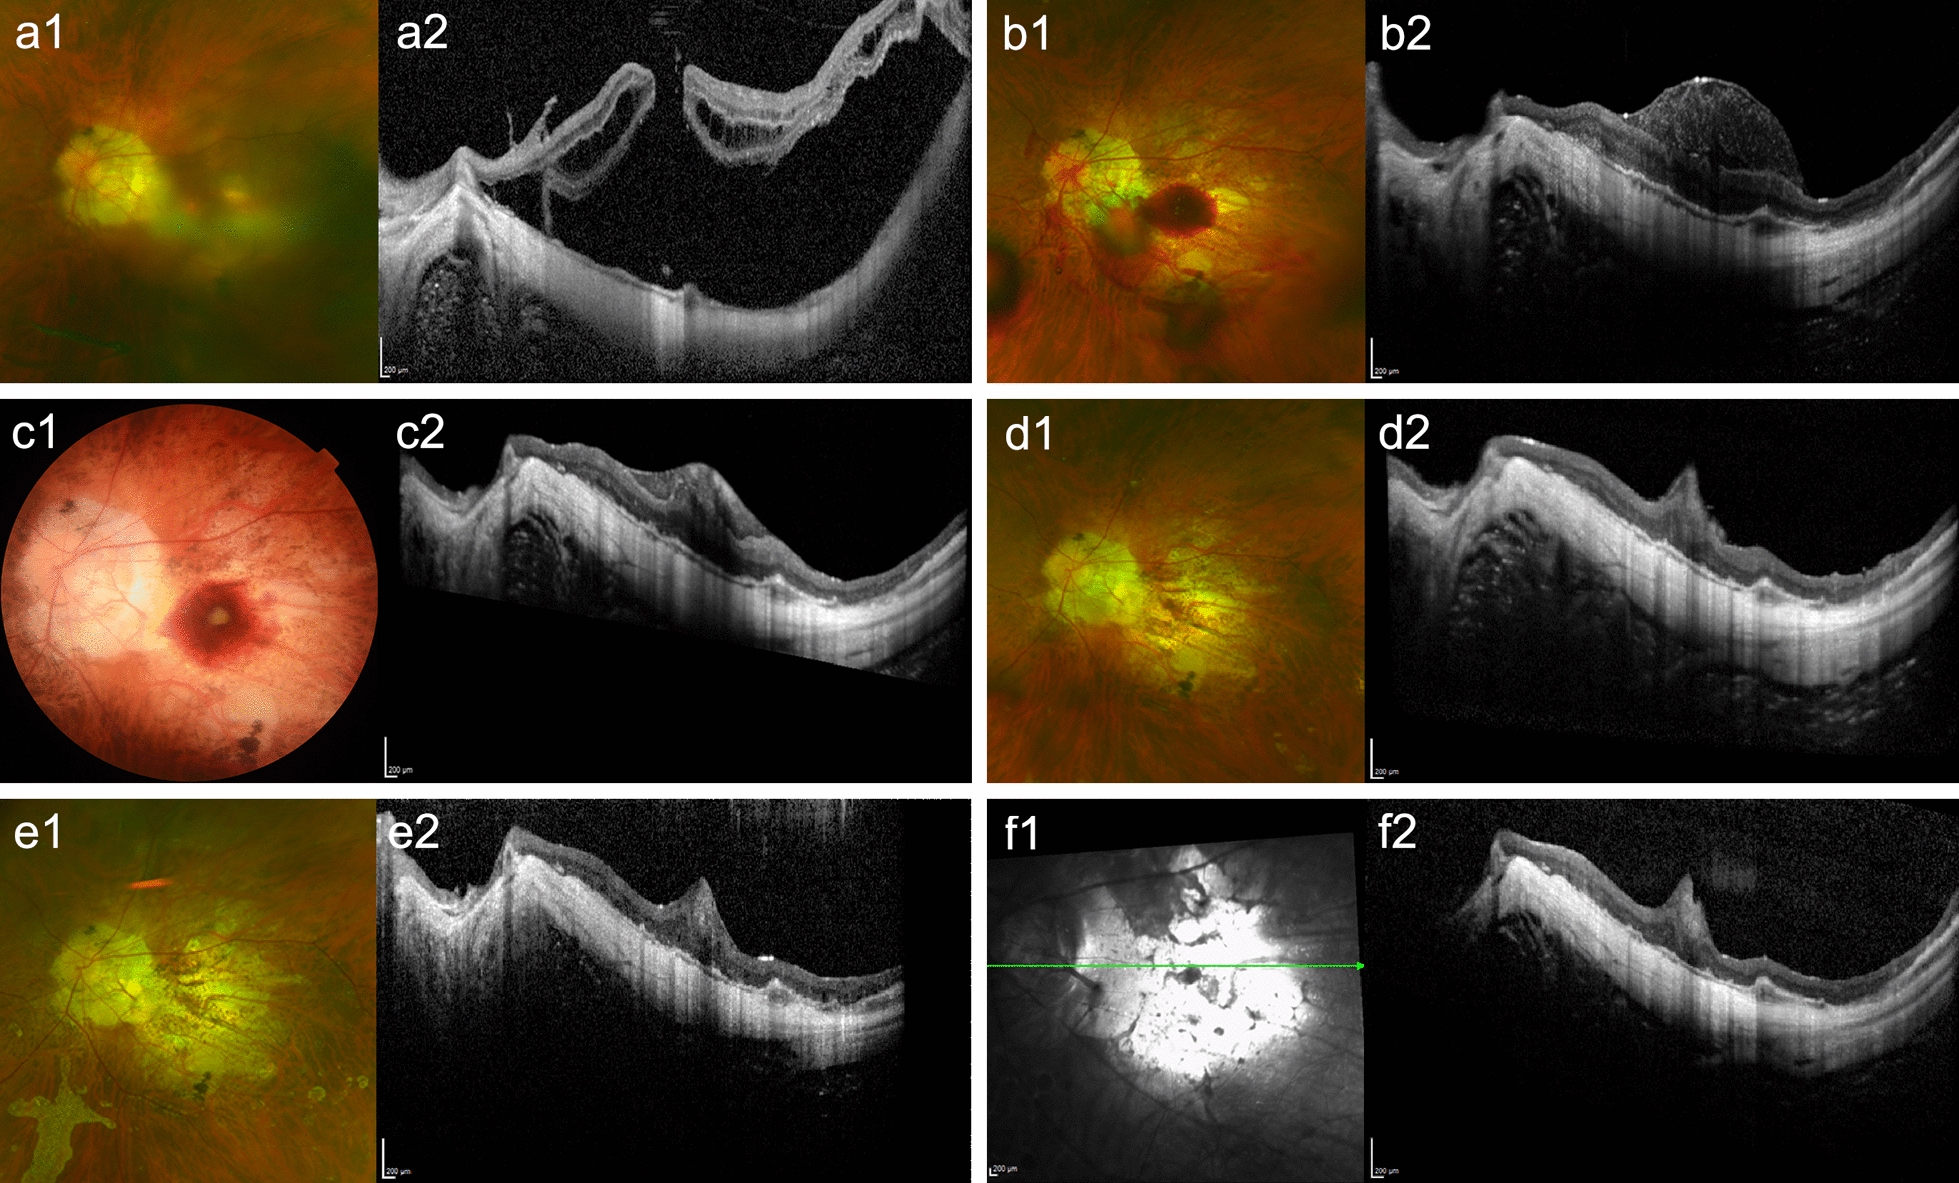

Background: To investigate the anatomical and functional outcomes of macular hole-associated retinal detachment (MHRD) after vitrectomy using the inverted internal limiting membrane (ILM) flap technique with autologous blood clot (ABC).

Methods: This retrospective observational study included 80 eyes with MHRD that underwent vitrectomy with ILM flap without (46 eyes) or with ABC (34 eyes). Fundus photography and optical coherence tomography were evaluated. The pre- and postoperative best-corrected visual acuities (BCVAs) and BCVA improvement were compared between the two groups.

Results: The MH closure rates after initial surgery were similar in the ILM flap group and ILM flap with ABC group [40 (87%) vs. 29 (85%) eyes, respectively]. The proportion of eyes with hyperreflective bridging tissue (HBT) was lower in the ILM flap group than ILM flap with ABC group [13 (32%) vs. 16 (55%) eyes, P = 0.060]. The postoperative improvement in BCVA was significantly better in the ILM flap group (P = 0.027). Multiple linear regression analysis revealed that preoperative BCVA was positively associated with postoperative improvement in BCVA (β = 0.638, P = 0.000), while the ILM flap with ABC technique was negatively associated with postoperative improvement in BCVA (β =  - 0.299, P = 0.039, adjusted r2 = 0.415).

Conclusions: The inverted ILM flap technique alone resulted in better foveal configurations and visual outcomes than the ILM flap technique combined with ABC in patients with MHRD.